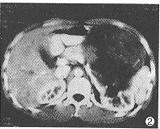

CT表现: 右肾上腺区一卵圆形囊状液性密度占位,CT值11.2HU,内有散在点状钙化,边缘 光整,囊壁后方与弧形受压的肾上腺实质相延续(图1);增强扫描囊内不强化,囊壁与肾上 腺均呈轻度强化(图2);下方的肾上极受压移位,轻度变形,但皮髓质完整(图3)。左前方的 胰头及上方的肝脏均为受压移位表现。

图1 CT平扫示右肾上腺区囊性占位,包膜光整,其内有多个点状钙化 图2 CT增强扫描示囊壁轻度强化,右肾上腺与囊肿关系密切(↑) 图3右肾受压、移位,但肾上极皮、髓质完整征[3]。而肝、肾囊肿内均极少出现钙化。对于一些极少见的 非典型肾上腺囊肿,由于囊内胶冻样物质CT值可达60HU左右[4],易误诊为肾上腺 的其他实性肿瘤,正确诊断需结合超声。